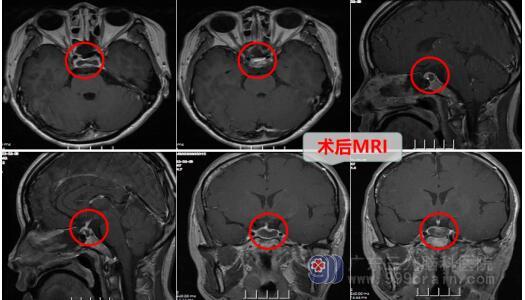

入院后完善相关检查,主管医生邓心情详细告知术前注意事项,可能会发生的并发症以及手术方案,可以不用开颅采用微创手术,即经鼻腔进入,术后不用填塞纱布,恢复快。家属明白手术风险后签字同意,择期进行了内镜经鼻鞍区rathke囊肿切开引流术,术程顺利,术后病人很快苏醒,没有发生原来担心的并发症,无尿崩,离子正常,鼻腔不用纱布填塞,病人呼吸顺畅。

邓心情医生解释,患者进行鞍区rathke囊肿内镜微创治疗,术后第三天出院,临床上充分做到快速康复的目的。